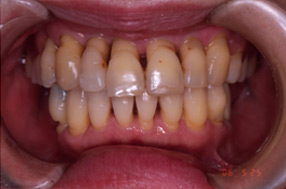

■歯周病治療例

歯周病の進行に伴う歯肉の

炎症と歯の移動が見られます。

歯周外科手術と同時に矯正で

歯周組織の再生と審美回復と

なりました。